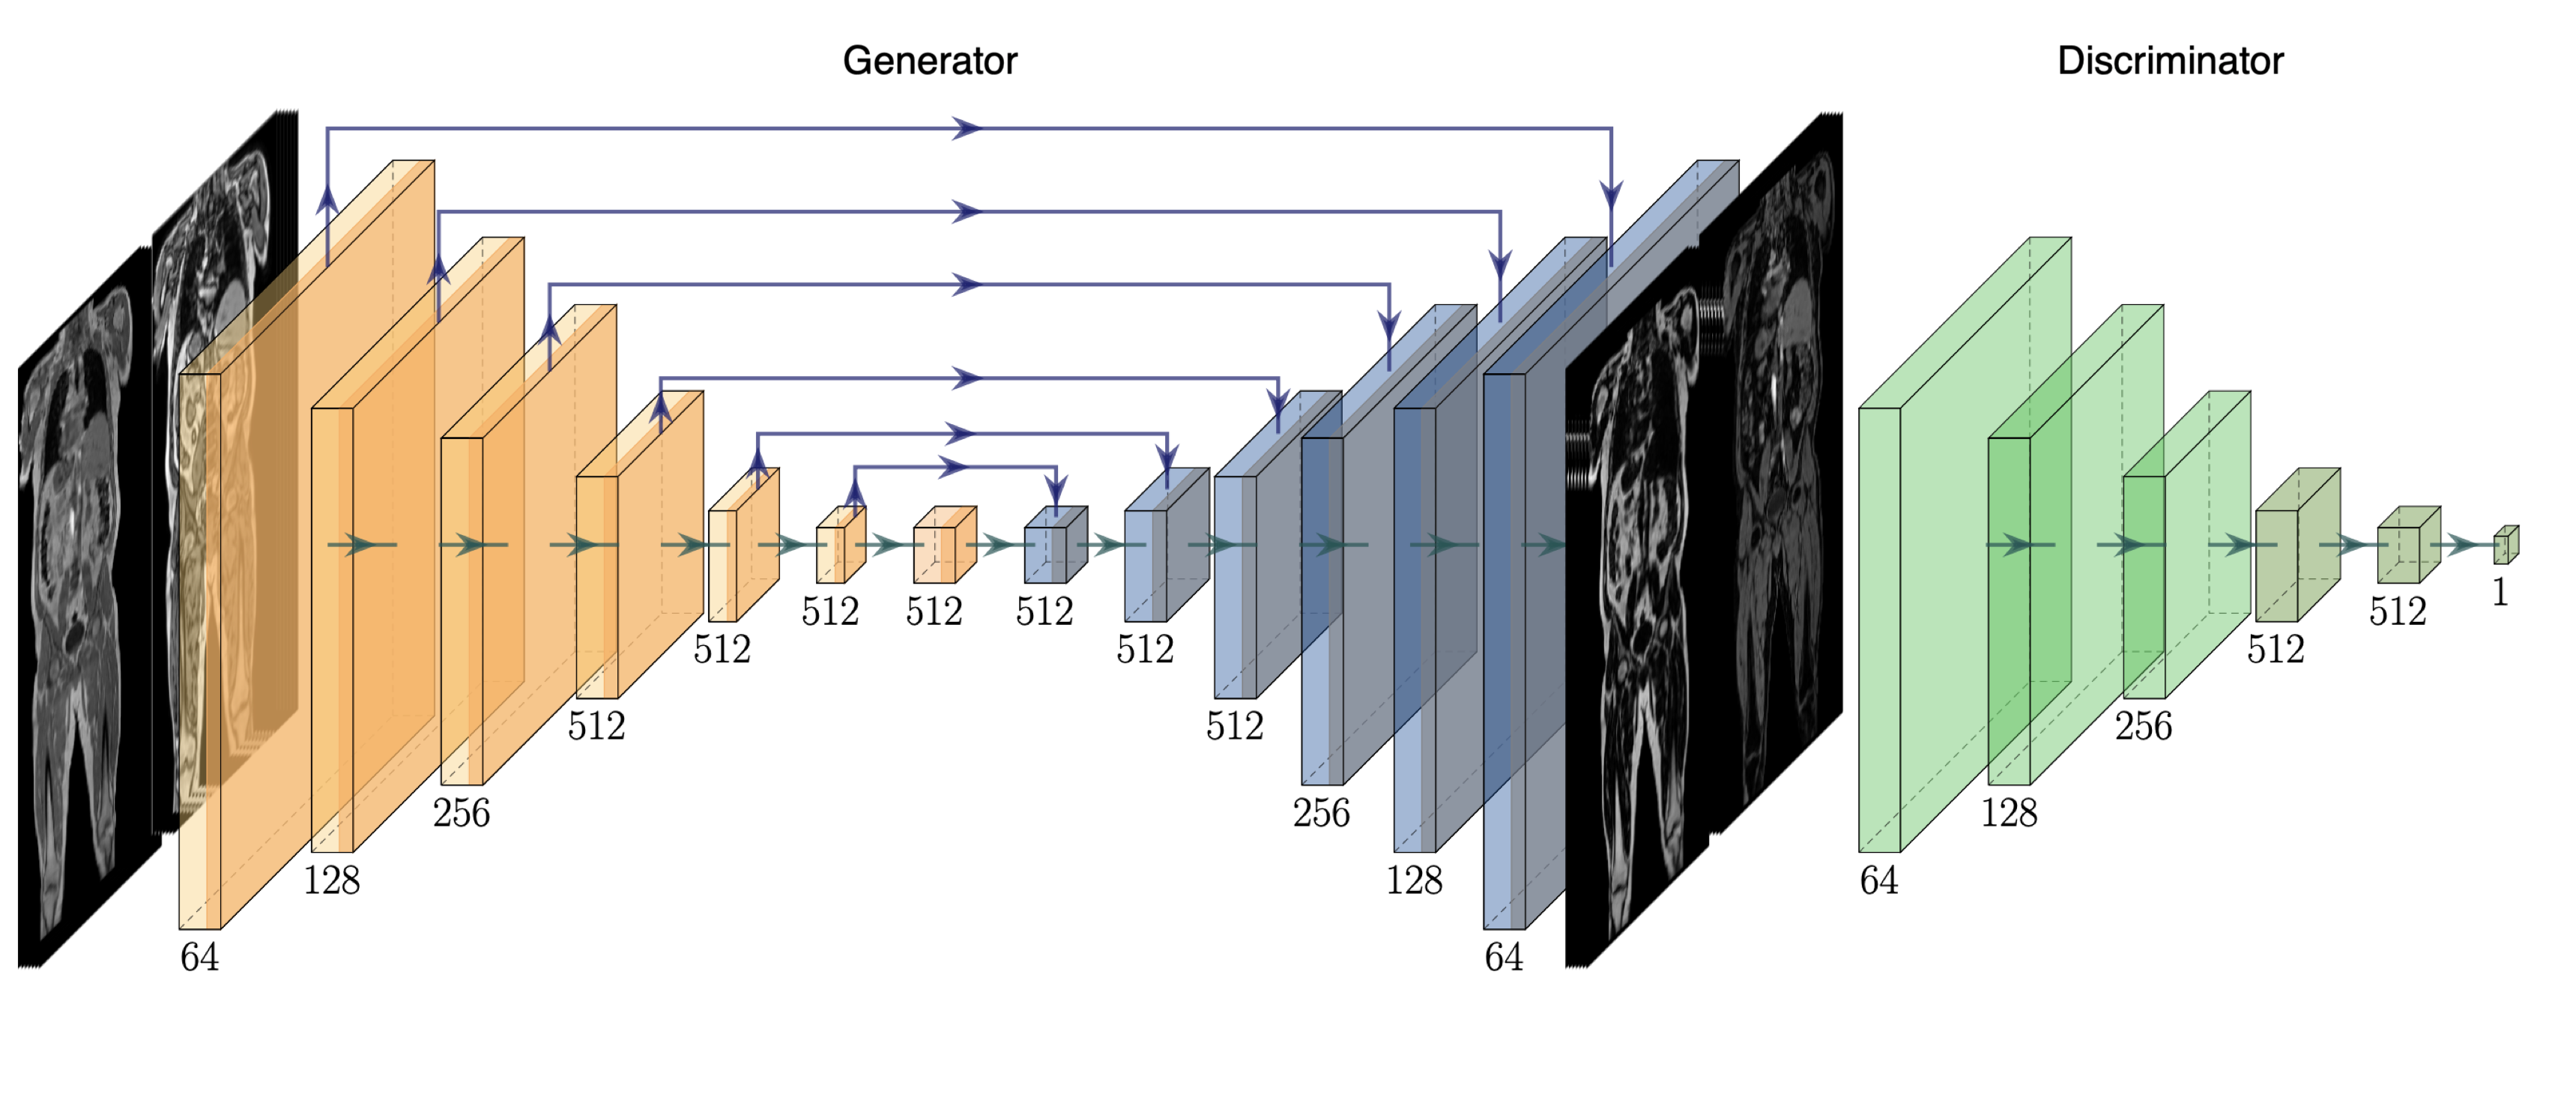

Fig. 3 shows the ground-truth data, predictions and their absolute difference for the fat and water channels of a participant in the testing set. Model predictions and the original data from the scanner for participants affected by various fat-water swaps are provided in Fig. 4. The examples were selected to illustrate the performance of our model in a variety of scenarios: data that are not affected by major swaps, data affected by swaps that cover an entire series in the acquisition (Fig. 4 a, c), as well as data displaying complex partial (Fig. 4 b, d, e) and/or boundary swaps (Fig. 4 f, g). The absolute difference images in columns 3 and 6 of Fig. 4 highlight where the original data have been affected by a fat-water swap in the scanner reconstruction but the model correctly predicted the fat and water channels. Fig. 5 provides examples of 3D segmentations using data that suffered from fat-water swaps (top row) and the segmentation when using our model predictions (bottom row) for the following organs and tissue (from left to right): abdominal subcutaneous adipose tissue, left kidney, spleen, and left/right iliopsoas muscles (red and green, respectively). The predictions shown in Figs. 3 and 4, as well as the underlying volumes used for the 3D segmentations in Fig. 5, are outputs of the final dual-input model, which performed the best across all of our experiments.

We have shown that our single- and dual-input models are able to predict swap-free fat and water volumes. Processing the entire neck-to-knee volumes, for example those found in the UK Biobank abdominal protocol, takes approximately eight seconds per scan. We have established the high quality of our results through quantitative metrics such as PSNR and SSIM (with average values consistently ) for the dual-input model in both cross-validation experiments (Table 1) and out-of-sample test data on final versions of the models (Table 2). We have shown qualitative performance on scans where the scanner software failed to adequately separate the fat and water channels during reconstruction in visual examples (Fig. 3) and by comparing to dixonfix to establish our method does not induce fat-water swaps (false positives). As a final qualitative validation we used the predicted channels as input to 3D segmentation models and have shown how the corrected data produces superior segmentations.